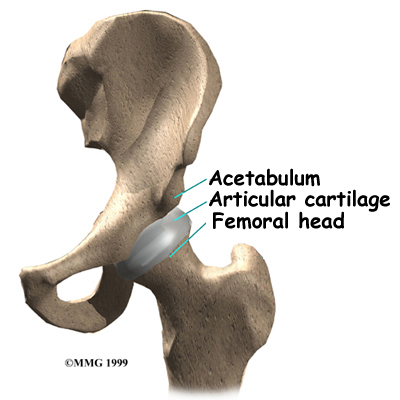

The femur is the large bone in the thigh. The ball-shaped femoral head fits into a socket in the pelvis, called the acetabulum. The femoral neck is a thinner part of the femur. It is the short section of bone next to the femoral head that connects the femoral head to the main shaft of the femur.